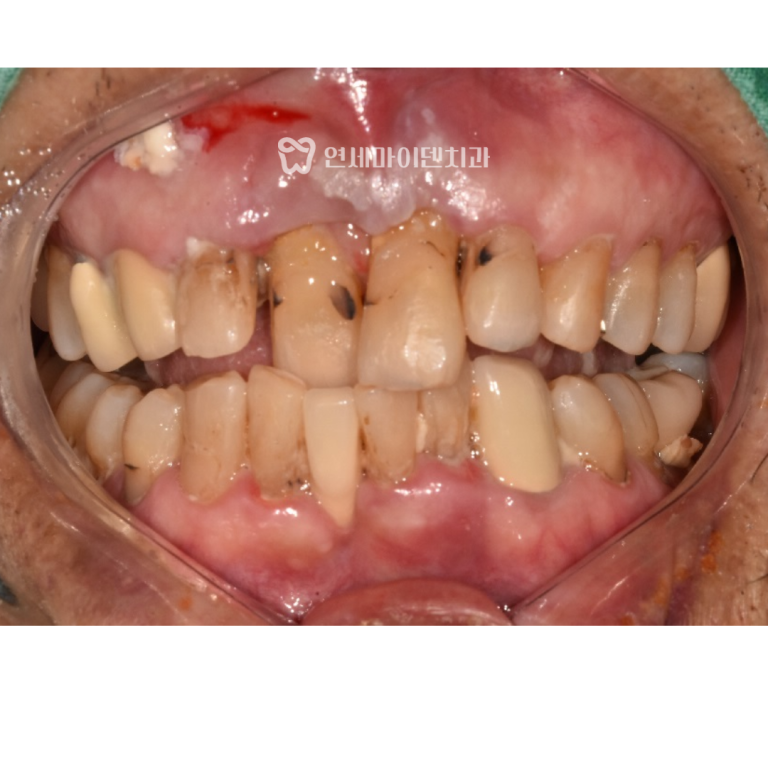

초진 구내 사진을 보면,

송곳니가 정상 위치에 있지 않고 유치가 남아 있어

치아의 높낮이가 맞지 않는 상태였습니다.

특히 오른쪽 위 어금니는 바깥으로 튀어나와

가위 교합을 형성하고 있었습니다.

또, 위아래 치아가 깊게 물리면서

아래 앞니도 삐뚤빼뚤한 모습이었어요.

남아있는 유치는 장기적으로 유지가 어려운 상태라서

발치 후 임플란트를 할 계획으로

치아 교정을 진행하기로 했습니다.